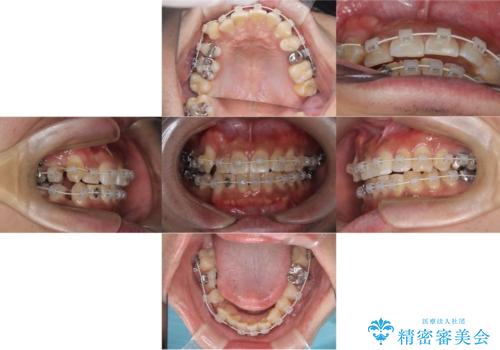

【ワイヤー矯正】八重歯と下の歯の凸凹を治したい

- ワイヤー矯正装置(審美装置)

- 主訴:右上の八重歯と、下の歯の凸凹を治したい

上顎右側第一小臼歯と下顎右側第一小臼歯を抜歯しワイヤー矯正を行いました。

右側2級、左側1関係だったため、右側上下第一小臼歯を抜歯し、ワイヤー矯正を行いました。

期間:2年6カ月